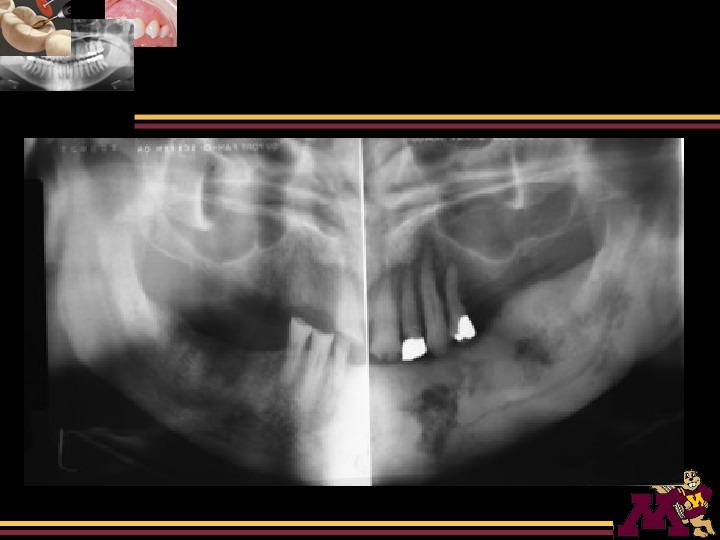

Radiographic Interpretation of Infections of Jaws Pericoronitis